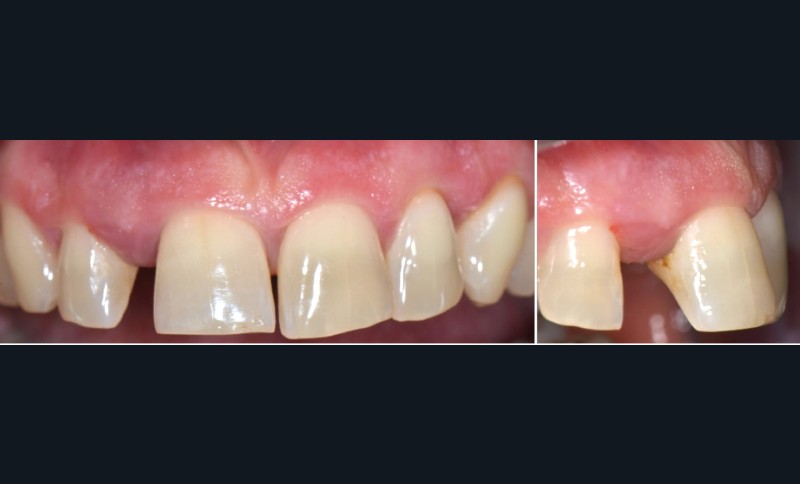

Formes cliniques

La MDP est dépendante de l’axe des forces appliquées à la dent. Ces forces peuvent ainsi conduire à des déplacements horizontaux, des versions (basculement par rotation) et/ou des égressions/extrusions (déplacement vertical seul, souvent retrouvé lors de la perte de dent antagoniste).

Des combinaisons de mouvements sont le plus souvent retrouvées, notamment lors de la perte du calage postérieur : déplacement horizontal et vertical, migration « en éventail ».